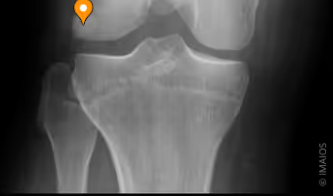

Articulatio genus - Kondylled

Knäleden, vilken typ?

Articulatio femorotibialis och articulatio femoropatellaris

Knäleden består av 2 sammansatta leder, vilka?

Femurkondylerna och tibiakondylerna

Articulatio femorotibialis, vilka delar?

Patella och trochlea femoris

Articulatio femoropatellaris, vilka delar?